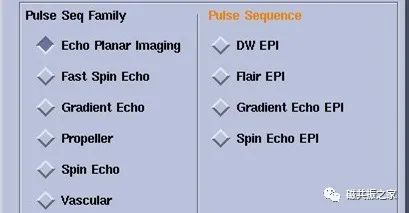

EPI序列:EPI技术是在一次RF激发后,采用正反梯度连续切换来读取采集信号,极大的缩短了扫描速度。

EPI的序列是目前成像速度最快的序列,该序列不局限于DWI、PWI等成像,还可以结合不同的序列得到不同权重的图像。